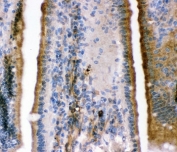

IHC-P: BK channel antibody testing of rat intestine tissue